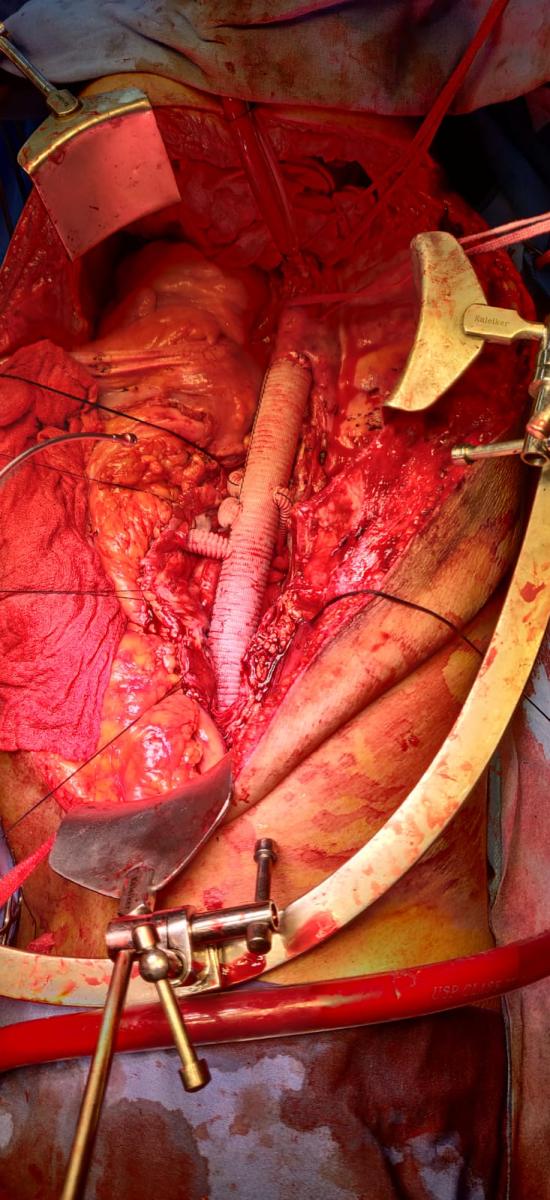

Photo Gallery Dr. Monika Gupta - Photo Gallery 7 5 2 8 6 Dr. Atul Kumar Gupta - Photo Gallery « ‹ of 3 › » Video Gallery